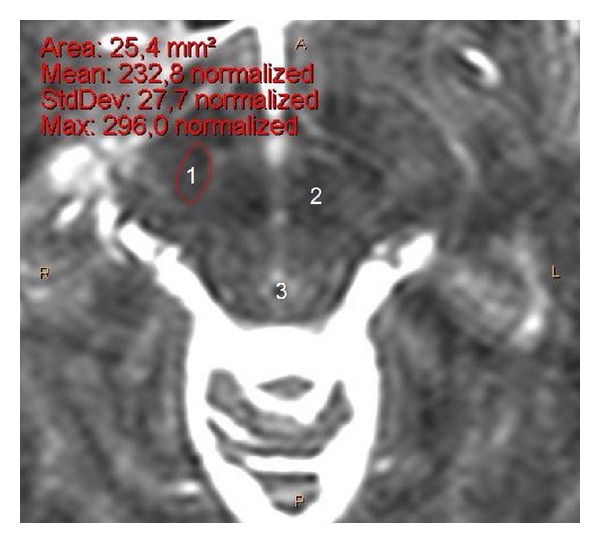

目的。我们的目的是提供一项以临床为导向的联合研究,重点研究人类STN的详细解剖结构,并在很大程度上考虑其靶向性。方法。在我们的成像研究中,我们使用了来自26名神经外科患者的脑磁共振图像(mri),并在我们的解剖研究中使用了来自18名尸体捐赠者的正常大脑的32个大脑半球。我们测量并分析了STN的尺寸(基于其立体定向坐标)。结果。在立体定向水平Z = -4时,mri上STN长度为7.7 mm,解剖标本上为8.1 mm。核磁共振成像宽度为6mm,解剖标本宽度为6.3 mm。MRI横切片平均可见STN 3.2片,最大尺寸为8.5 mm。mri上关节间距离26.3 mm,解剖标本上关节间距离27.3 mm。个体间STN的宽度和长度差异有统计学意义

Purpose. Our purpose was to provide a combined clinically oriented study focused on the detailed anatomy of the human STN, with great respect to its targeting. Methods. For our imaging study, we used cerebral magnetic resonance images (MRIs) from 26 neurosurgical patients and for our anatomic study 32 cerebral hemispheres from 18 normal brains from cadaver donors. We measured and analyzed the STN dimensions (based on its stereotactic coordinates). Results. At stereotactic level Z = -4, the STN length was 7.7 mm on MRIs and 8.1 mm in anatomic specimens. Its width was 6 mm on MRIs and 6.3 mm in anatomic specimens. The STN was averagely visible in 3.2 transverse MRI slices and its maximum dimension was 8.5 mm. The intercommissural distance was 26.3 mm on MRIs and 27.3 mm in anatomic specimens. We found statistically significant difference of the STN width and length between individuals <60 and ≥60 years old. Conclusion. The identification of the STN limits was easier in anatomic specimens than on MRIs and easier on T2 compared to T1-weighted MRIs sections. STN dimensions appear slightly smaller on MRIs. Younger people have wider and longer STN.